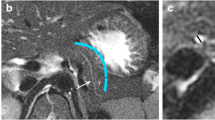

Two-year-old girl. She was diagnosed as a case of type II congenital CC using the 3D model method (b, d, f) and as a suspected case of type II congenital CC using MRCP (a, c, e). Images presented a clear morphology, the level of location of the CC, and its relationship with the adjacent structures, such as the gallbladder neck, common bile duct, and distal part of the duct (# indicates the gallbladder; * indicates a diverticulum)

In the present study, most of the Todani classification results were similar between the 3D model and the MRCP imaging; however, some differences in the classification were observed with the MRCP imaging. One patient had a cyst protruding from the right middle aspect of the CBD and there was a confluence of the gallbladder duct with the distal part of the CBD; this patient was diagnosed as a type I CC with MRCP and as type II CC with the 3D model. Another case was diagnosed as type II CC with the 3D model which showed the protrusion of the structural cyst from the right posterior aspect of the CBD and confluence of the gallbladder duct with the proximal part of the cyst. Accordingly, the gallbladder was pushed and moved forward. These pathological changes were missed on MRCP imaging due to the overlapping structures leading to misdiagnosis.